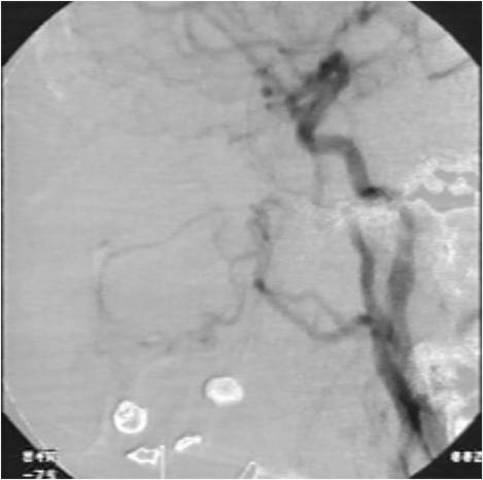

Arteriografía y embolización.

Método selectivo para aquellos pacientes donde se sospecha de una malformación arterio-venosa como causa de sangrado. No se utiliza de forma rutinaria.(https://youtu.be/8o1YY9f_W-c)